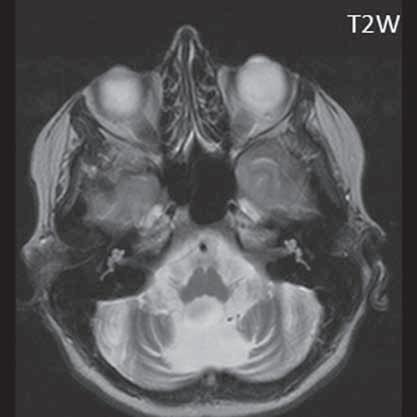

I.1.8 Dandy-Walkerova malformace (D-W variant, D-W komplex, D-W spektrum )

Zobrazení

D-W malformace je charakterizována hypoplazií vermis mozečku, rozšířením IV. mozkové komory, která se často cysticky vyklenuje dorzálně a může imitovat arachnoidální cystu, rozšířením zadní jámy lební a vysokým úponem tentoria s confluens sinum nad lambdovým švem. Okcipitální kost může být vlivem tlakových změn remodelována, existují i případy s porušením její kontinuity a encefalokélou. Hydrocefalus pozorujeme v 80 %, častá je přítomnost dysgeneze corpus callosum, schizencefalie.

D-W variant byl vyčleněn pro případy, kdy všechny základní příznaky nemusí být plně vyjádřeny nebo může některý zcela chybět. Bývá přítomna hypoplazie mozečku, což je dominantní příznak, IV. komora je obvykle rozšířena, někdy pozorujeme, že tvarem připomíná na axiální řezu „klíčovou dírku“, zadní jáma lební naopak rozšířena nebývá.

Obr. I.1.8e Dandy-Walkerovo spektrum (hypoplazie vermis, IV komora je rozšířená a široce zeje) (snímky zapůjčeny z archivu as MUDr J Lisého, CSc )

Obr. I.1.8f Dandy-Walkerovo spektrum (hypoplazie vermis, IV komora je rozšířená a široce zeje) (snímky zapůjčeny z archivu as MUDr J Lisého, CSc ); stejný pacient jako na obr I 1 8e

Obr. I.1.8g Dandy-Walkerovo spektrum (hypoplazie vermis, IV komora je rozšířená a široce zeje), (snímky zapůjčeny z archivu as MUDr J Lisého, CSc ); stejný pacient jako na obr I 1 8e, f